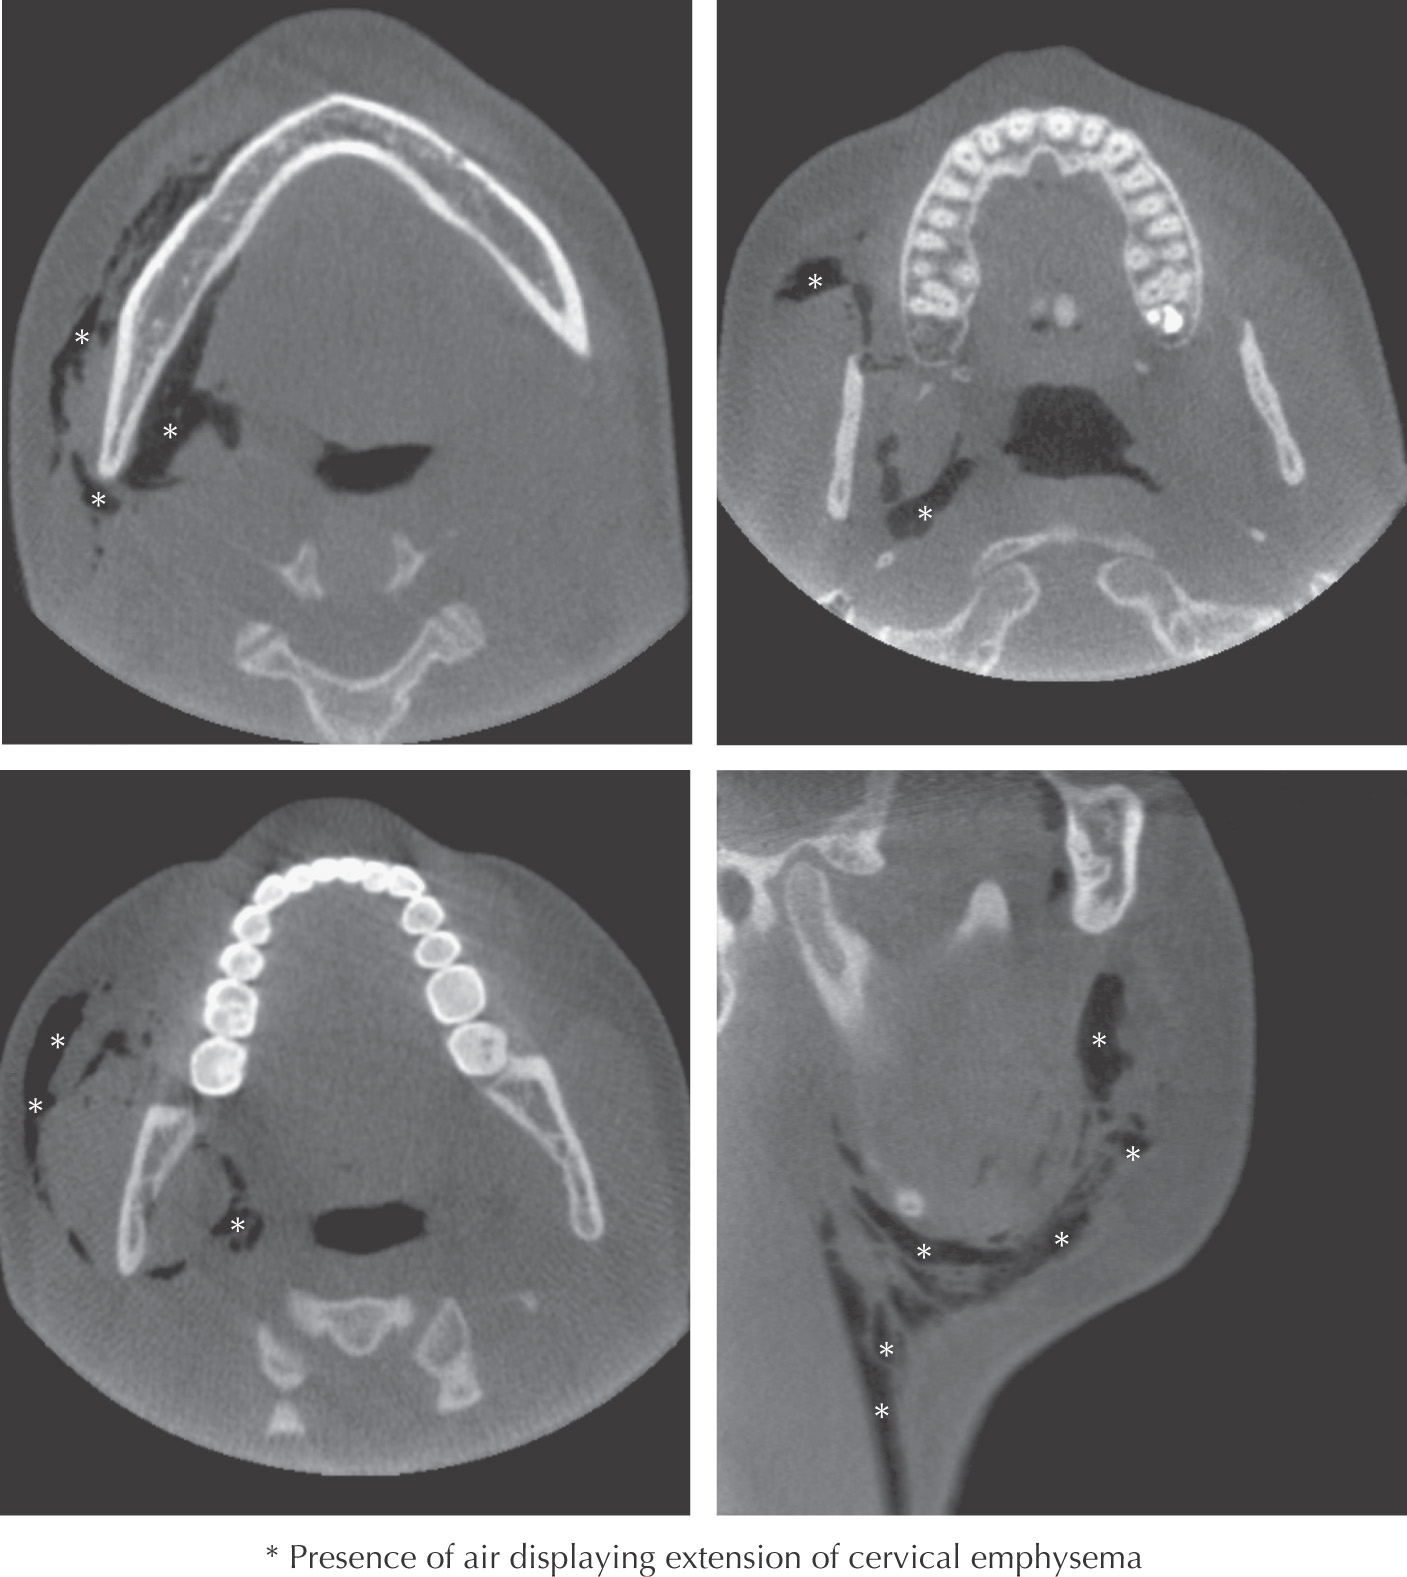

Introduction of gas deep to the skin which may be due to trauma, iatrogenic, or infection.

Some causes include fractures of the head and neck, introduction of air from a high speed dental drill, and surgical procedures such as root canals and extractions of mandibular 3rd molars

In the head and neck, cervical emphysema can spread via the fascial planes

May be benign or fatal, depending on the spread